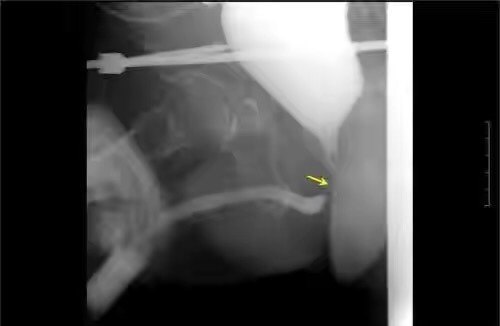

曾铭强 湖南省人民医院泌尿外科主治医师 膀胱尿道造影x线检查发现后尿道闭锁的部位和长度。 三维ct成像显示膀胱尿道的立体结构、与直肠的关系,以及骨盆的稳定性和恢复情况。 车祸、工伤容易导致重要脏器破裂出血、全身多处骨折,如果发生严重的骨盆骨折,还容易并发男性尿道断裂、尿道出血,导致后尿道狭窄或闭锁。发生尿道狭窄的病人,常常出现尿频、尿急、排尿困难等症状,长期梗阻可导致肾功能衰竭等;如果发生尿道闭锁,尿液无法排出,往往需要先行尿流改道、留置膀胱造瘘管,待病情稳定后再接受尿道复通手术。 55岁的黄先生是湖南娄底人,5个月前在工地上被小型挖掘机碾压下腹部,导致骨盆多处骨折、左股骨骨折、失血性休克。在当地医院接受了急诊骨盆骨折固定手术、大量输血等。经过5个月的康复治疗后,患者为求尿道复通手术经当地医生介绍,找到湖南省人民医院泌尿二科曾铭强博士,以“创伤性后尿道闭锁”收住院。 入院后,经过膀胱尿道造影X线检查发现后尿道闭锁的部位和长度,了解了患者尿道损伤部位没有假道、瘘管发生;骨盆和膀胱尿道三维CT成像显示膀胱尿道的立体结构、与直肠的关系,以及骨盆的稳定性和骨折的恢复情况。 术前诊断中,利用膀胱软镜分别从尿道外口进入观察断端远段尿道、从膀胱造瘘口进入观察断端近段尿道的情况,发现前列腺尖部有一片状的结石,也没有发现尿道损伤部位有假道和瘘管形成。通过充分的术前准备后,曾铭强医师等为患者成功实施 “后尿道闭锁段切除+端端吻合术”。术中通过充分暴露、彻底清除瘢痕组织、止血等措施后,行远、近端尿道无张力吻合。 患者术后恢复好,48小时后即可下床适量活动,术后1周出院。